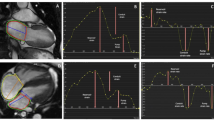

Three types of tissue arrhythmias were observed: (i) early afterdepolarisations, (ii) extrasystoles between triggered AP, and (iii) stimulation-independent, spontaneous depolarisations in the form of couplets (Fig. 2A). Other pro-arrhythmic electrophysiological tissue abnormalities included impaired APD shortening with increasing stimulation frequency, resulting in a failure to follow increased stimulation rates of 2, 3, and/or 4 Hz (Fig. 2B), and APD alternans (Fig. 2C), which were both frequently observed in TOF but not in ASD tissue (Fig. 1).

Pro-arrhythmic electrophysiological tissue abnormalities in myocardial samples and their association with action potential (AP) shape. A Example traces of tissue arrhythmias: early afterdepolarisations (left, indicated by yellow star), extrasystoles (middle, indicated by blue circle), and stimulation-independent spontaneous depolarisations (right, grey arrows indicate stimulation timing). B Example of impaired action potential duration (APD) shortening at stimulation frequency of 3 Hz (grey arrows indicate stimulation timing). C Example APD alternans with blue arrows indicating alternating APD. aBar graphs indicate one data point per recording location; p-Values represent association over all frequencies for a given AP parameter and occurrence of electrophysiological tissue abnormality in mixed linear effects model. arr. arrhythmias, AUC90 area under the curve at 90% repolarisation, imp. shorten. impaired APD shortening, stim. freq. stimulation frequency

Evaluating the association of pro-arrhythmic tissue abnormalities with AP parameters demonstrated a significant association of tissue arrhythmias with larger APA, longer APD20, APD50, and APD90, and larger AUC90, of impaired APD shortening with slower dV/dtmax, longer APD20, APD50, and APD90, and larger AUC90, and of APD alternans with longer APD20 (Fig. 2, Table 2).